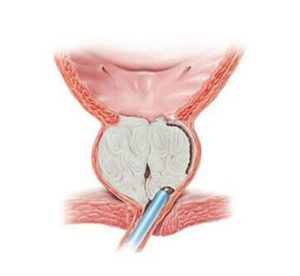

Vezica urinară este un rezervor în care urina ce provine de la nivelul rinichilor este stocată înainte de a fi evacuată în momentul micțiunii. Prostata este o glandă situată sub vezical. Pentru ca urina să fie evacuată din vezică în timpul micțiunii, ea trebuie să traverseze prostata printr-un canal numit uretra prostatică. Uretra este deci canalul prin care urina este expulzată din vezică. Prostata este constituită din două părți: centrul prostatei care este traversat de uretra și care este zona unde apare hipertrofia (sau adenomul de prostată). Această zonă centrală este înconjurată de o parte externă numită zona periferica.

Prostata este un organ sexual care este situat la ieșirea din vezică și prin intermediul căruia urina trece. Odată cu înaintarea în vârstă prostata îmbătrânește de asemenea, fapt ce duce la apariția a ceea ce se numește ‘’hipertrofie benignă de prostată’’ sau ’’hiperplazie benignă de prostată’’. Această hipertrofie se datorează apariției adenomului de prostată ce se dezvoltă la nivelul glandei. Este o afecțiune foarte frecventă la bărbații peste 50 de ani.

Intervenția care vă este propusă se numește enuclearea endoscopică a prostatei. Ea este practicată cu ajutorul unei fibre si a unui laser. Acest tratament este realizat fără nici o incizie, ci doar pe căile naturale urinare (transuretral). Intervenția constă în lărgirea canalului uretrei prin rezecția adenomului ce se găsește în centrul prostatei. Zona periferică a prostatei este prezervată.

Această intervenție este realizată sub anestezie generală sau rahidiană. Medicul urolog introduce la nivelul canalului uretral un aparat numit endoscop care îi permite vizualizarea uretrei si reperarea prostatei. Cu ajutorul unei fibre laser medicul urolog poate introduce endoscopul între adenomul de prostată și capsula prostatei. Astfel, făcând tot turul adenomului de prostată, medicul urolog detașează adenomul de capsula prostatei și împinge adenomul în vezica urinară. Adenomul complet liber este extras cu ajutorul unui instrument ce se numește morcelator, care permite morcelarea (tăierea) adenomului de prostată în mici fragmente ce pot fi extrase prin aspirare prin interiorul endoscopului.